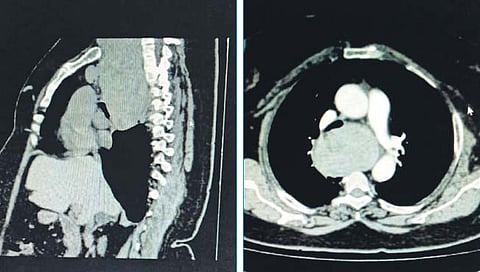

त्यात छातीच्या आतील भागात हृदयाच्या आणि श्वासनलिकेच्या मागच्या भागापर्यंत मोठा रेट्रोस्टर्नल थायरॉईड (गलगंड) पसरल्याचे समोर आले. तो किती आहे, हे पाहण्यासाठी डॉक्टरांनी सीटी ब्रॉन्कोस्कोपी करुन श्वासनलिकेची तपासणी केली.

त्यात श्वसन नलिकेवर थायरॉईडच्या गाठीमुळे दाब पडत असून श्वास घेण्यास त्रास होत असल्याचे समजले. त्या महिलेचा गलगंड खूप मोठा असून त्याला काढण्यासाठी रुग्णाला (स्टर्नोटोमी) छातीच्या किचकट शस्त्रक्रियेची शक्यता लागणार होती.